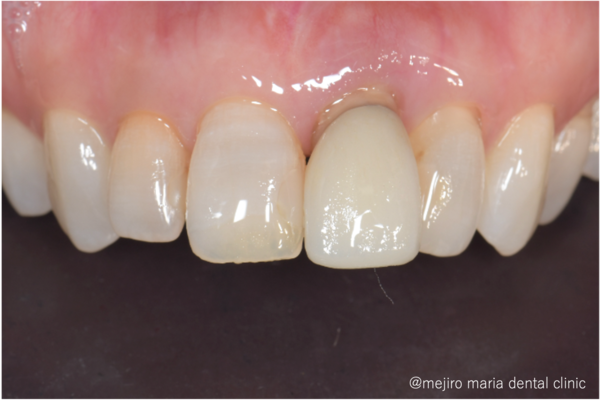

この症例では抜歯、歯槽堤保存術後4ヶ月ほど経ったところで補綴治療へと移行しました。

先述の「接着性ブリッジ」を選択しましたのでほとんど歯を削っていません。高い接着力を持つ材料を使い、隣の歯にセラミックの歯を貼り付けているのです。

歯槽堤保存術を行ったことでほとんど歯茎は凹むことなく、自然な見た目で治療を終えることができました。